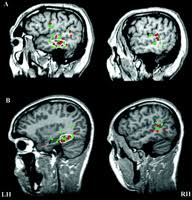

Le traitement chirurgical

En cas d’épilepsie pharmacorésistante, c’est-à-dire lorsque des crises d’épilepsie persistent malgré un traitement médicamenteux bien pris, une intervention neurochirurgicale peut être envisagée, en fonction de :

la fréquence et l’ancienneté des crises épileptiques ;

leur retentissement sur la vie du patient ;

l’existence d’un foyer épileptogène précis (zone cérébrale où se déclarent des crises récurrentes, liées par exemple à une tumeur ou une malformation engendrant des lésions).

Avant toute intervention, on réalise un bilan approfondi pour mieux localiser le foyer épileptogène et vérifier s’il peut être enlevé, sans risque de handicap lié à l’ablation d’une zone du cerveau.

Pour réaliser ce bilan, on utilise l’imagerie cérébrale fonctionnelle (ensemble de techniques d’imagerie médicale permettant d’analyser le fonctionnement du cerveau). Une fois le bilan de l’épilepsie terminé, la décision thérapeutique est prise par une équipe pluridisciplinaire (chirurgien, neurologue, neuropédiatre, radiologue).